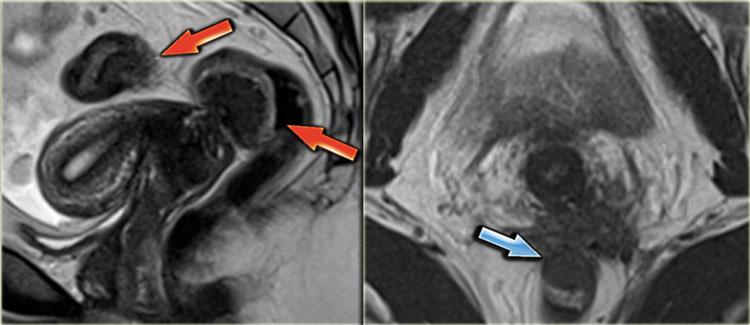

Hình ảnh T2W cho thấy hai tổn thương giảm tín hiệu hình nan quạt (mũi tên đỏ).

Những đặc điểm này điển hình cho các tổn thương lạc nội mạc tử cung xâm lấn lớp cơ thành ruột.

Ngoài ra còn có phù nề dưới niêm mạc, biểu hiện là tăng tín hiệu ở phía lòng ruột của thành ruột.

Hình ảnh T2W cho thấy hẹp khu trú trực tràng do lạc nội mạc tử cung xâm lấn toàn chu vi.